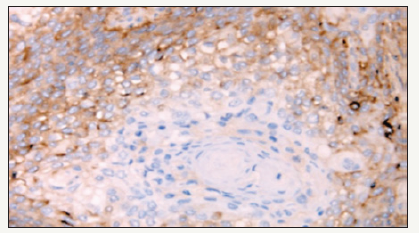

Figure 4:Immunohistochemistry for CD133 (a) and CD44 (b) markers of stem cells, isolated by tumor biopsy.

Calif. Et al. published data representing a direct link between existing genetic alteration and malignant phenotypic progression in OSCC and presented them as a model of genetic progression. This model is supported in vivo experimental animal studies of carcinogenesis of the skin indicating that exposure to the initial agents causes cellular changes that are retained within the tissue over an extended period of time. Another hypothesis supported by both in vitro and in vivo experiments suggests that oncogenic events may occur in keratinocytes derived from primitive stem cells and can cause renewal of stem cell capacity for self-regeneration and reduce terminal differentiation. More than 90% of all human neoplasms originate from the epithelium. In normal epithelial tissues the stem cells are usually found in the basal layer and they perform an asymmetric division that allows self-restoration of stem cells and differentiation in terminal cells. The degree of carcinoma differentiation depends on the ratio of undifferentiated tumor stem cells, the maturity stages of most cells in the main tumor mass and the ability of some cells to differentiate themselves. The hierarchical structure of stem cells present in the human epithelium indicates that the stem cells are a unique long-term cell and the only cells capable of accumulating the necessary number of genetic changes for malignant development. Obviously, tumor growth is associated with pattern and amplification patterns similar to those in normal tissues. There are six acquired carcinoma marks-unlimited replication of cells, self-sufficient growth, avoidance of apoptosis, insensitivity to signals against growth, sustained angiogenesis, invasion of surrounding tissues and metastases. Identification of carcinoma stem cells in head and neck tumors is the main goal of the stem cell biology agenda as well as the detection of key factors involved in self-renewal and differentiation patterns. However, it must be taken into account that there are still open controversies about the role of CSC in the development and progression of the tumor. In addition, biomolecular markers that define less subpopulations of the CSC show great variability that makes it difficult to characterize them and study tumor biology. Preliminary immunohistochemical results of some continuous studies (Figure 4) on the primary HNSCC sections provide additional evidence for a development hierarchy in HNSCC similar to that in normal squamous mucous membranes. Good to moderately differentiated HNSCC demonstrate a cellular organization with a basal layer differentiation with immature morphology cells towards the atypical layer with the appearance of more mature squamous morphology [9].

An analysis of the distribution of CD44 in well or moderately differentiated tumors suggests a clear redistribution topography in favor of strong positive layers of basal cells in contrast to several keratinized and differentiated cells in the higher layers in which this marker was absent (Figure 5). These findings provide additional evidence that HNSCC is organized into a development hierarchy as predicted by the CSC theory of carcinogenesis and indicating the possible value of CD44 in the HNSCC [9].

Figure 5:An analysis of the distribution of CD44 in moderately or highly differentiated tumors, indicating a clear topographic distribution of CD44-positive basal cell cells, while in a more differentiated and keratinized tissue this marker is absent.